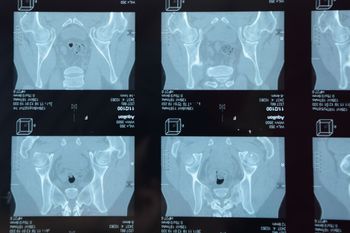

An international physician group writing in the British journal Annals of the Rheumatic Diseases, has updated recommended parameters that constitute lesions in the sacroiliac joints of patients with spondyloarthritis. The definitions of capsulitis, enthesitis, fat lesion and erosion were revised and new definitions were developed for joint space enhancement, joint space fluid, fat metaplasia in an erosion cavity, ankylosis and bone bud.

In this slideshow, we highlight 12 recommendations for assessing MRI lesions on the sacroiliac joints of patients with spondyloarthritis. The recommendations were made by the Assessment of Spondyloarthritis International Society (ASAS) MRI working group and published in the British journal Annals of the Rheumatic Diseases earlier this year.

Bone erosion, fat in joint spaces (backfill), and ankylosis visible on MRI could help identify women with axial spondyloarthritis, investigators wrote in a research article published last month in Arthritis & Rheumatology.